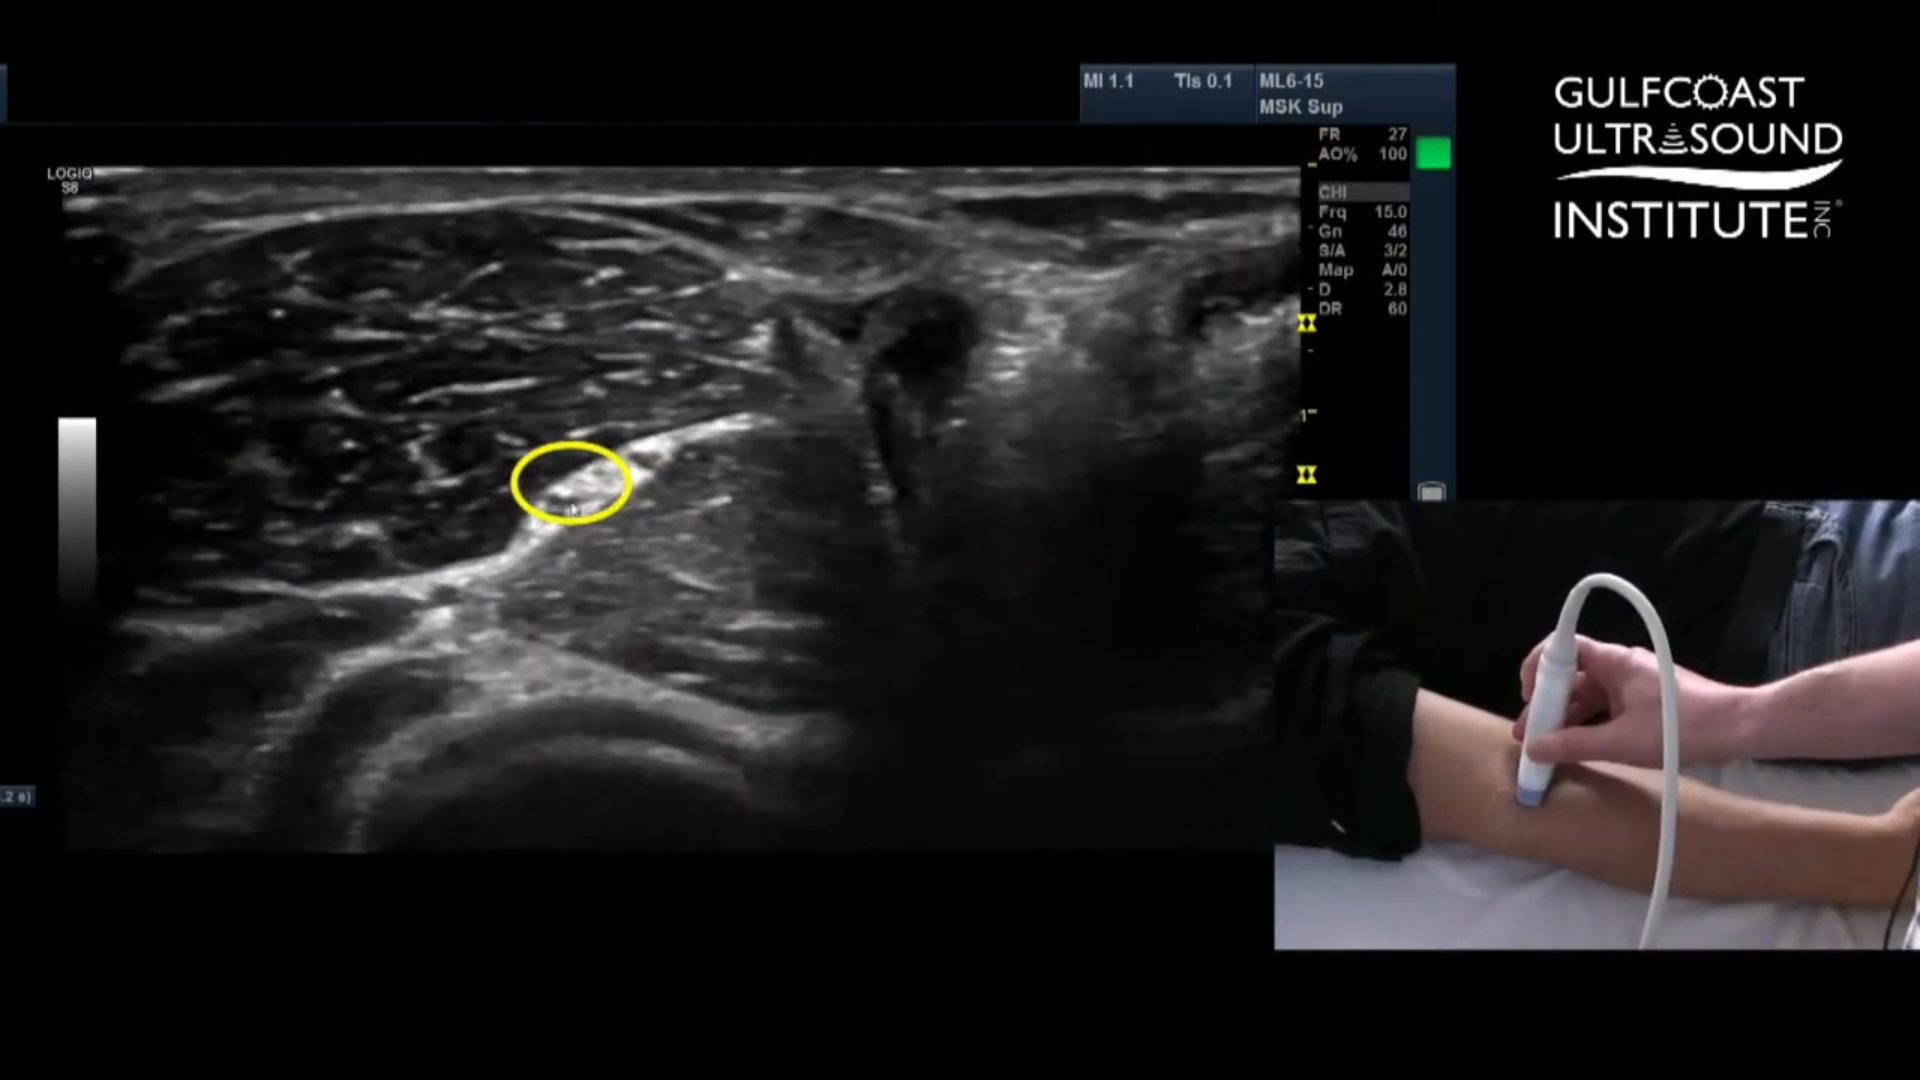

Locating and Blocking the Radial Nerve

Now for the radial nerve. This one behaves a bit differently. It splits just distal to the elbow, so you'll want your patient to slightly rotate their forearm into a "thumbs-up" position. This hand orientation gives you better access and a cleaner acoustic window. Place your probe along the mid-arm and start sliding it laterally. As you angle and tilt your probe slightly, you’ll see the radial nerve pop up between two muscle layers, nestled right in the fascial plane. It’s a distinct and satisfying view once you catch it.